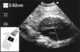

Aneurysm of abdominal aorta or its branches

The abdominal aorta is the largest artery in the abdominal cavity. As part of the aorta, it is a direct continuation of the descending aorta (of the thorax). [Source: Wikipedia ]